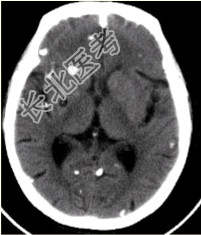

- [材料题] 患者男,45岁。头痛、癫痫10余年。查体:无发热,双侧肢体肌力正常。脑电图示双侧额颞叶棘波放电。CT表现如下图。

- 多项选择题1.可能的诊断为

A、包虫

B、囊虫

C、结核

D、转移瘤

E、真菌感染

F、甲状旁腺功能减低